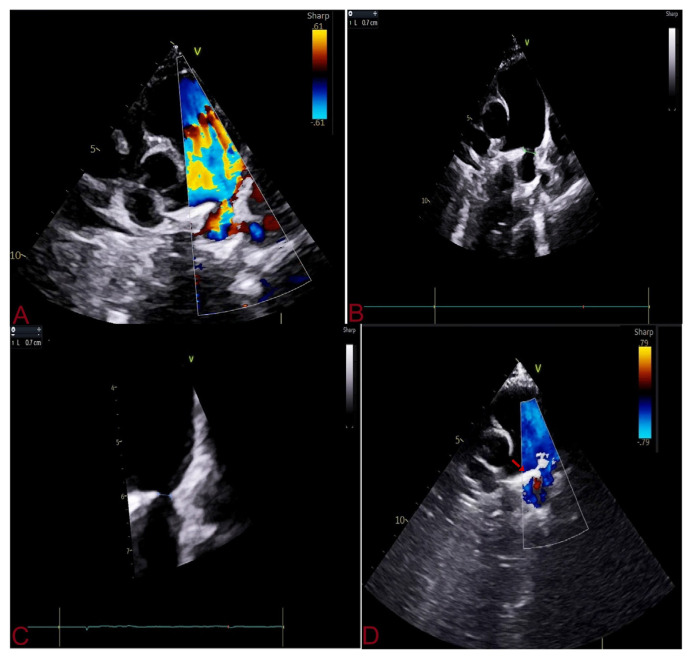

Method: In this prospective, non-randomized study, all consecutive patients with PDA undergoing transcatheter closure at LPS Institute of Cardiology, Kanpur, India between January 2019 and June 2024 were evaluated. TCC was performed using anatomical and haemodynamicl landmark without aortogram, and device was deployed through antegrade route only. Transthoracic echocardiography with colour-Doppler imaging was used to confirm position of the device before final deployment. Primary outcome was procedural and fluoroscopy time, and major complications (access site complications, device embolization, residual shunt ≥ grade 3, haemolysis, flow acceleration in left pulmonary artery and descending thoracic aorta, and death). Success was defined as complete closure of shunt without any major complications.